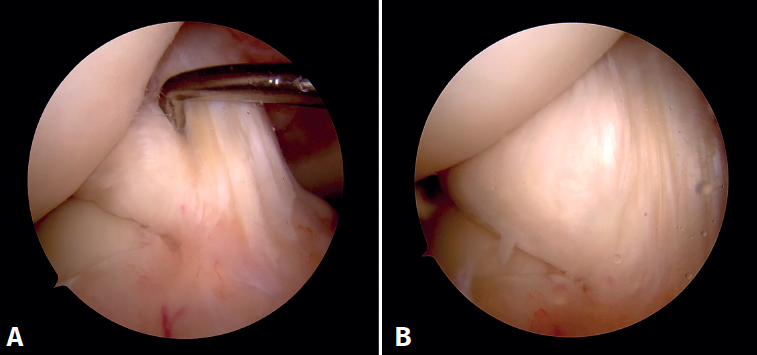

Figura 4. Visión artroscópica desde el portal anterolateral. Se introduce a través del portal anteromedial el instrumental. A: inicio del desbridamiento del quiste con un basket artroscópico; B: se continúa el desbridamiento del quiste con un shaver de 4 mm respetando las fibras del ligamento cruzado anterior sano.

En el postoperatorio se autorizó la movilidad y la carga progresiva con bastones según la tolerancia. En ambos pacientes la sintomatología dolorosa y las restricciones de movilidad articular se resolvieron completamente. No se realizó RM de control en ninguno de los dos casos.

Figura 5. Visión artroscópica desde el portal anterolateral. A: tras el desbridamiento se observa que no existe pinzamiento del espacio articular femorotibial lateral en posición “de cuatro” a 90° de flexión; B: palpación de la tensión del remanente del ligamento cruzado anterior.